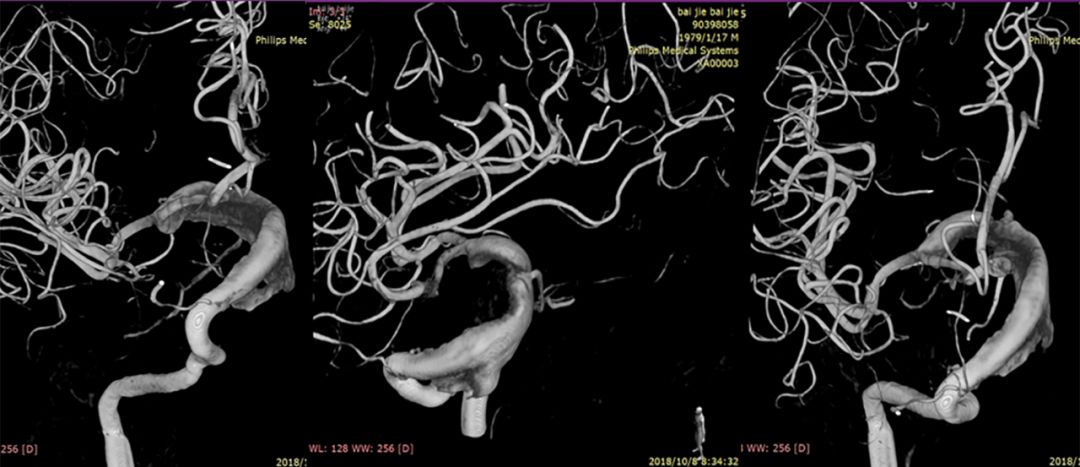

(2)左颈动脉造影见大脑前动脉抬高,右侧颈内动脉球囊闭塞试验见前交通动脉开放,M1段显影不良,考虑后交通供血较强(图2)。

图2

(3)后循环造影及右侧颈内动脉球囊闭塞试验,提示后交通供血较明显,可见动脉瘤显影,无法闭塞颈动脉,选择行动脉瘤栓塞术(图3)。

图3